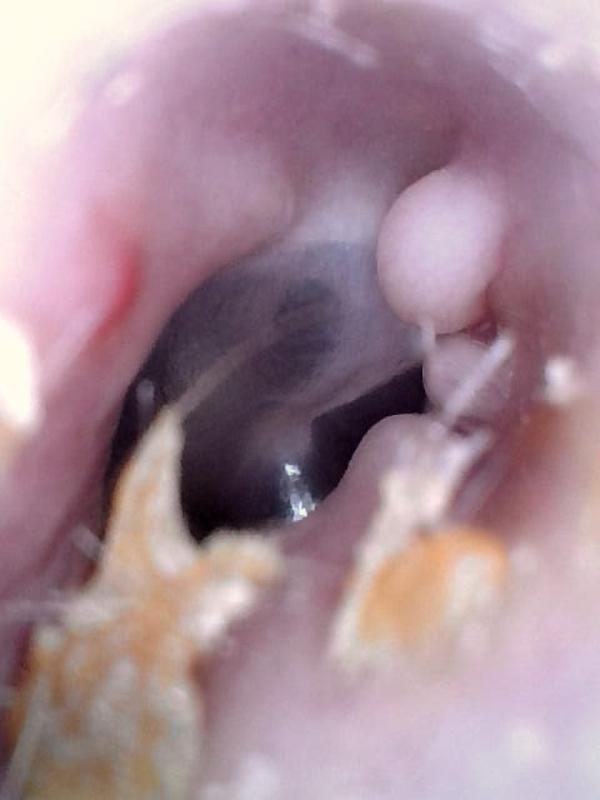

Surfer’s Ear (Exostoses)